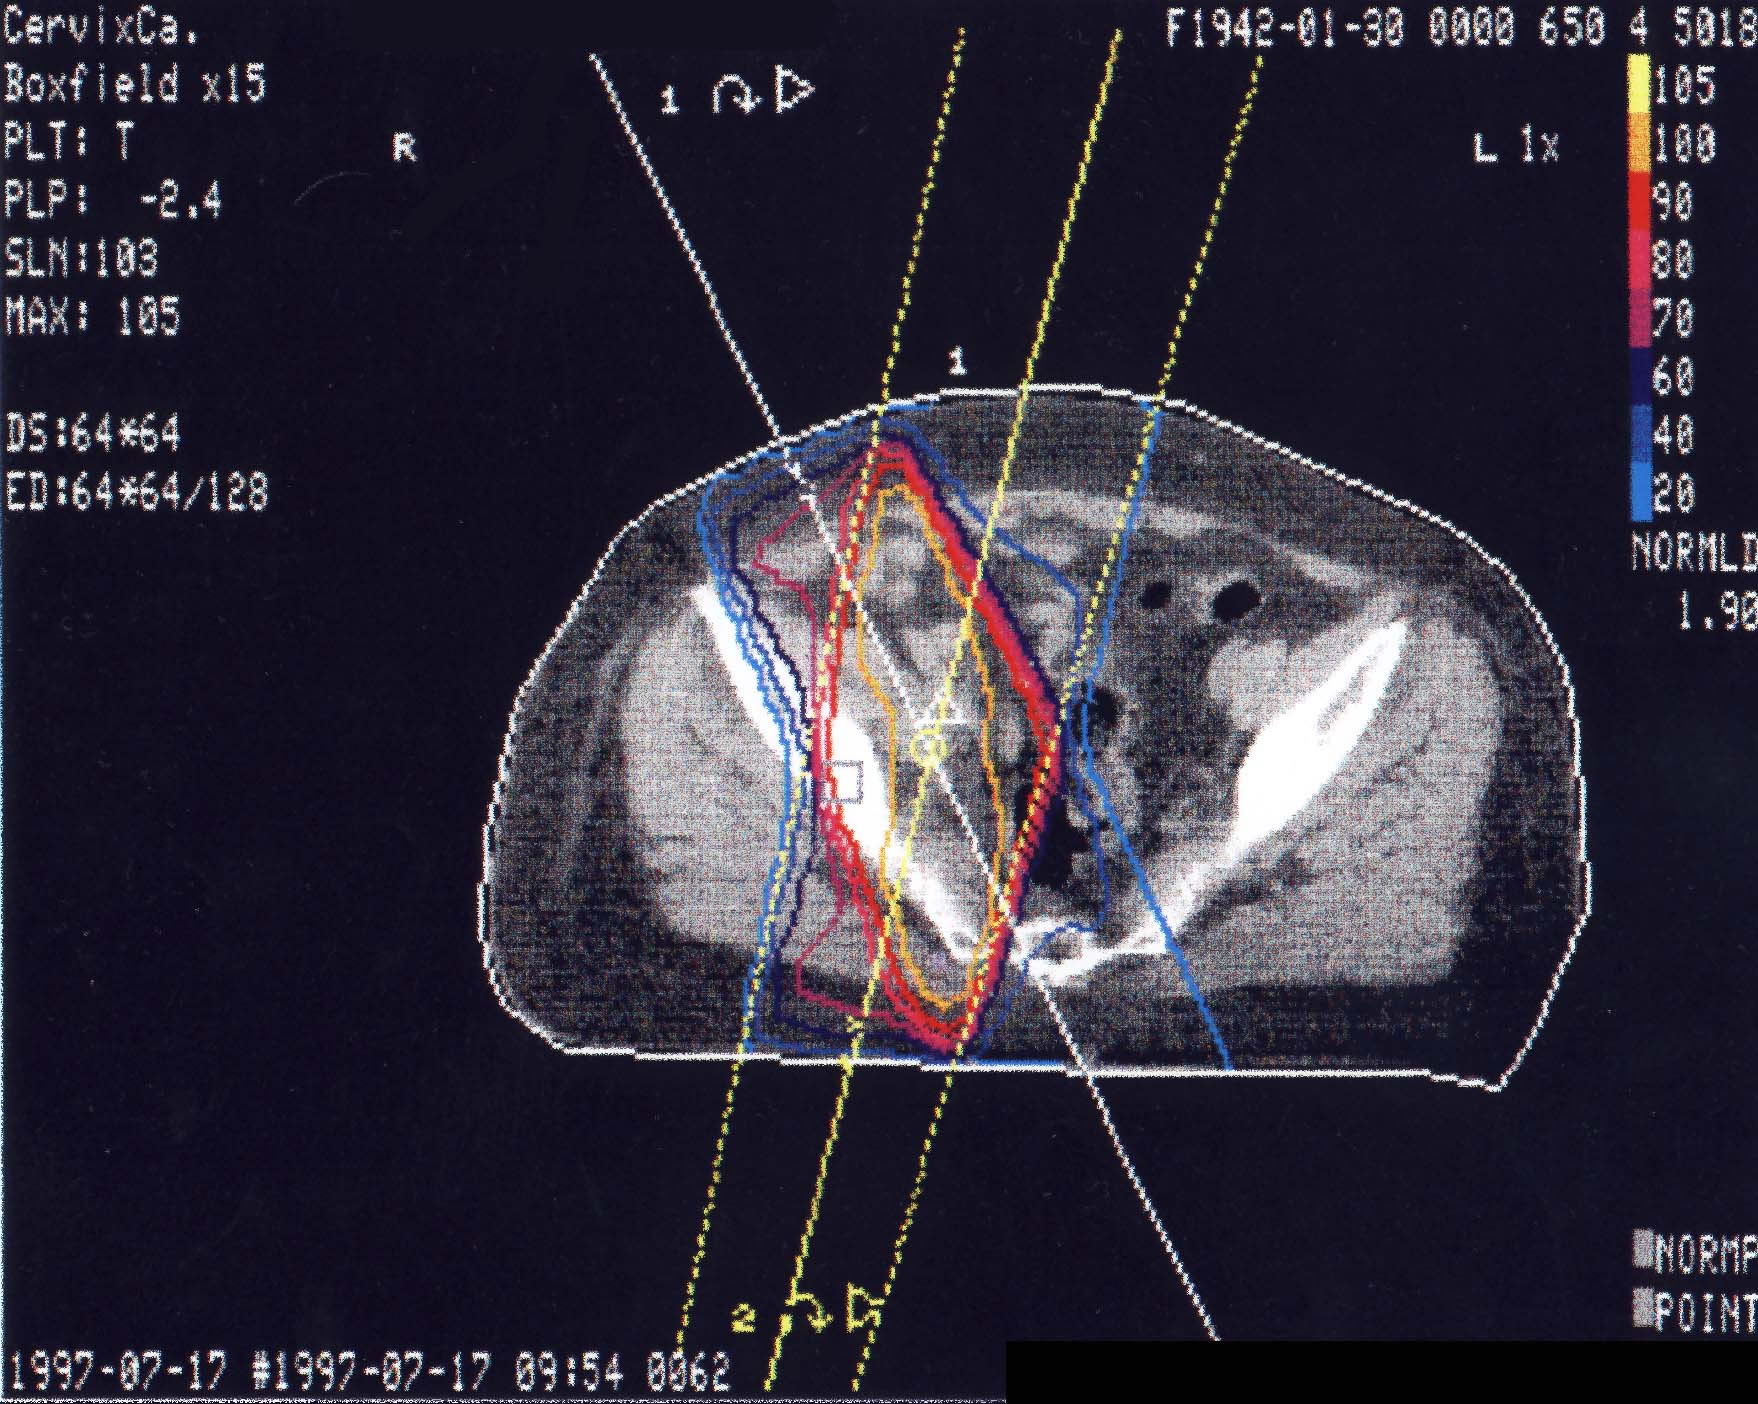

Gynäkologische Tumore des Beckens: Bestrahlungsplan

Bestrahlungspläne